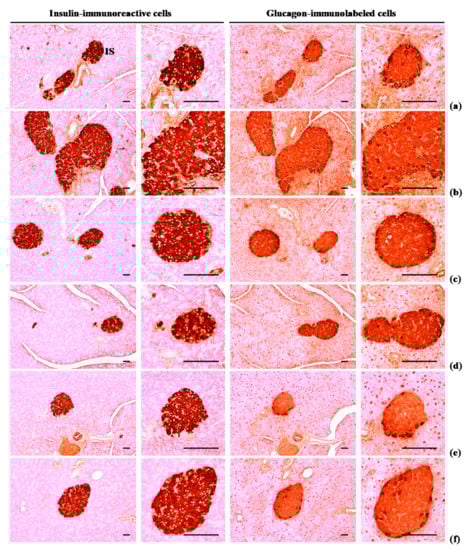

Using the avidin-biotin-peroxidase (ABC) detection method and guinea pig polyclonal insulin (Abcam, Cambridge, UK) or rabbit polyclonal glucagon (Abcam, Cambridge, UK) antiserum, serially sectioned pancreatic tissues were immunostained. Briefly, the incubation in methanol and 0.3% H2O2 for 30 min was performed to block the activity of endogenous peroxidase; Normal horse serum blocking solution (Vector Lab., Burlingame, CA, USA) in a humidity chamber for 1 h was used for non-specific immunoglobulin binding. This was followed by incubation with ABC reagents (Vectastain Elite ABC Kit, Vector Lab., Burlingame, CA, USA) and biotinylated universal secondary antibody (Vector Lab., Burlingame, CA, USA) in a humidity chamber for 1 h at room temperature. In the end, the sections were interacted with a peroxidase substrate kit (Vector Lab., Burlingame, CA, USA) at room temperature for 3 min. Between steps, all samples were rinsed three times using 0.01 M phosphate-buffered saline. Cells that exhibited more than 20% immunoreactivity (compared with other naïve cells) were defined as positive; the average numbers of glucagon- and insulin-immunoreactive cells scattered in 1 mm2 of pancreatic parenchyma were calculated by an automated imaging analysis program, and insulin/glucagon cell ratios were also calculated; Ratin of insulin/glucagon cells = (mean of insulin-immunoreactive cells/mean of glucagon-immunoreactive cells). When performing the analysis, the histopathologist was blinds to the group allocation.

3.2.4. Effects of WL on Pancreatic Islet Glucagon- and Insulin-Immunoreactive Cells

The numbers of glucagon and insulin-immunoreactive cells and ration of insulin/glucagon cells were higher (p < 0.01) in HFD control group than in intact control group. Though, these abnormal increases in glucagon and insulin-immunostained cells and their ratio were normalized in a significant and dose-dependent (p < 0.01) manner by each of the three WL dosages and by metformin, compared with the results in HFD control group. In particular, 50 mg/kg WL and metformin inhibited the HFD-induced hyperplasia of insulin and glucagon-immunoreactive cells, and increased insulin/glucagon cells (Table 8; Figure 7). The mean numbers of insulin-immunoreactive cells in HFD control group were increased 1117.60% as compared to intact control group, but they were decreased −50.87, −86.63, −75.35, and −53.46% in metformin 250 mg/kg, WL 200, 100, and 50 mg/kg groups as compared to HFD control group. The mean numbers of glucagon-immunolabeled cells in HFD control group were increased 532.74% as compared to those of intact control group, but they were decreased −28.83, −76.50, −61.19, and −30.56% in metformin 250 mg/kg, WL 200, 100, and 50 mg/kg groups as compared to HFD control group. The ratio of insulin/glucagon cells in HFD control group was increased 89.87% as compared to intact control group, but it was decreased −29.52, −42.26, −36.58, and −32.61% in metformin 250 mg/kg, WL 200, 100, and 50 mg/kg groups as compared to those of HFD control group.